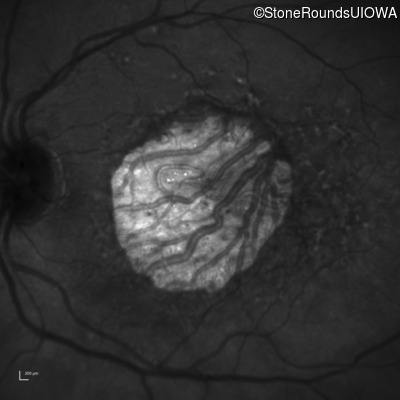

Infrared Fundus Photograph - Right - 20/160 -1

Exemplar